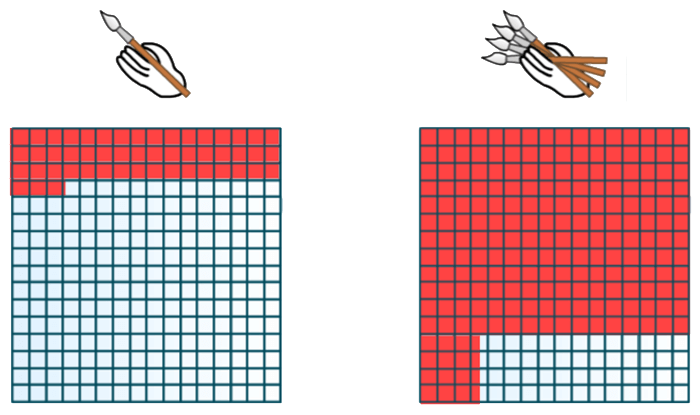

In reality, the space of one TR is needed to fill one line and we have as many lines as indicated by the phase matrix. Another parameter involved is the ETL or echo train length or turbo factor as it is sometimes called. It is the number of lines of the Fourier space filled in at each TR. The number of Nex is the number of times the Fourier space will be filled. A good analogy for the number of Nex’s is a painter repainting a wall: the more coats of paint, the better the result but more time is required to fully paint the wall.

Example: The parameter is equivalent to the number of paintbrushes used by the painter: the more brushes (the higher the number), the more the lines of the Fourier space can be filled in during one TR and so the entire Fourier space will be filled in more rapidly.

In our example, if we use 4 brushes (turbo factor or ETL = 4), our Fourier space will be filled in 4 times more rapidly. This is a concept we discussed when we learned about the fast spin-echo sequence.